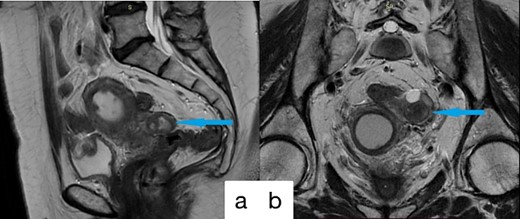

A 61-year-old female patient was admitted to the hospital presenting with lower abdominal discomfort and purulent discharge from the genital tract. The patient was diagnosed CRC 3 years ago, staged as pT3N0M0. She underwent robotic low anterior resection with D3 lymph node dissection as primary treatment, followed by surveillance without adjuvant chemoradiotherapy. At the 6-month postoperative follow-up, local recurrence at the anastomotic site was detected, prompting initiation of radiotherapy with a total load of 50 Gray and chemotherapy with capecitabine 1000 mg/m2 per day for 2 months anв resulted in full response. Subsequent Magnetic Resonance Imaging (MRI) evaluation posttreatment revealed complete clinical remission. During 17 months follow-up after surgery, MRI revealed no evidence of disease progression in the colon, alterations in the left fallopian tube, enlargement of the uterine cavity and cervical canal, and soft tissue hyperplasia within the uterine cavity (Fig. 1). The result of laboratory tests revealed no breast cancer gene 1 (BRCA1) or BRCA2 gene mutations, Carbohydrate antigen 19–9 (CA 19–9) levels at 12.7 U/ml, Carcinoembryonic antigen at 1.3 ng/ml, and cancer antigen 125 (CA-125) at 63.2 U/ml. Uterine cavity biopsy identified G2 adenocarcinoma growth in the uterine corpus. During a subsequent surgical procedure, the presence of a tumor in the left fallopian tube was identified, leading to an enlarged resection of the uterus and adnexa (Fig. 2). Histopathological examination indicated tumor invasion of the left fallopian tube, along with infiltration into the superficial myometrial layers, not exceeding 1 mm, wall, particularly in the endo-tubal region.

Preoperative MRI imagines; (a) sagittal; (b) coronal; alterations in the left fallopian tube, enlargement of the uterine cavity and cervical canal, and soft tissue hyperplasia within the uterine cavity.